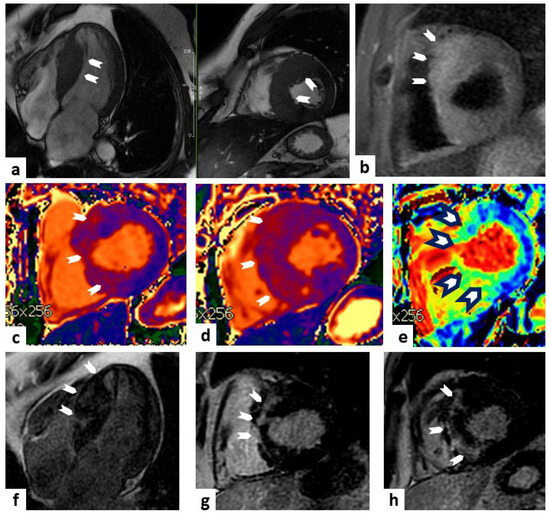

6. Cardiac Amyloidosis

9. Cardiac Sarcoidosis